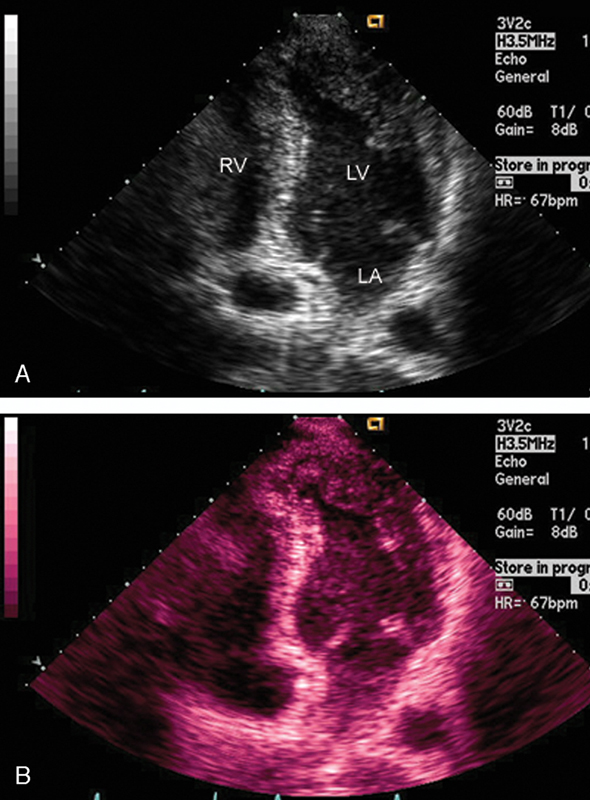

فحوصات تشخيصية لبعض امراض القلب والشرايين التاجية